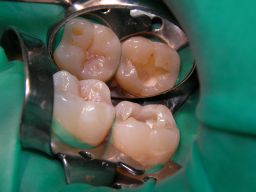

| Schließlich eine 22jährige, junge Dame, die trotz Aufklärung über die vermutlich etwas eingeschränkte Haltbarkeit eine weiße Kompositfüllung statt Amalgam wollte: | |||||||||||||||||||||||||||||||||||||||||||||||||||||||||||||||||||||||||

![]() | Am Ende waren es sogar 3, nicht nur 2 Füllungen (wer sieht die 3.?). Das grüne Latexgummi ist Kofferdam (=Spanngummi), der manchmal die Arbeit erleichtert, weil er den Speichel fernhält. Zuzahlung für die Kassenpatientin 2 * 30 . Mit Speichelfilm sind solche Füllungen im Alltag nicht mehr zu erkennen. |